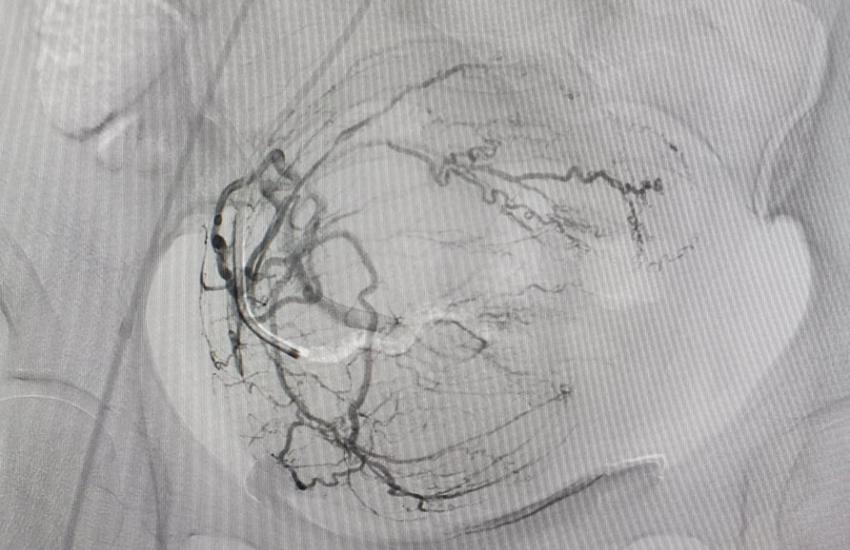

ЕМА - СУЧАСНА та ЕФЕКТИВНА альтернатива хірургічному лікуванню при фіброміомі матки:

- проводиться малоінвазивним способом, тобто через прокол в руці або нозі пацієнтки;

Фахівці Черкаської обласної лікарні проводять ЕМА на сучасному обладнанні експертного класу з використанням якісних перевірених матеріалів.